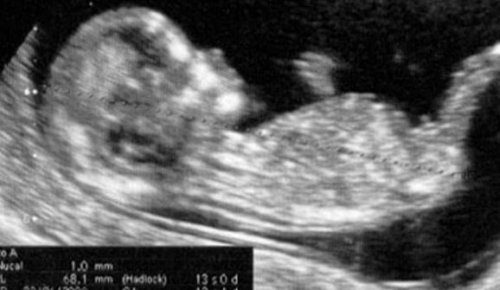

Under den 13:e veckan av graviditeten kan ultraljudet för slutet av första trimestern fortfarande utföras, om det inte redan har gjorts.

Detta är det sista steget i den serie kontroller som modern måste göra efter det att graviditeten först bekräftats.

Det här är den punkt där utvärderingen av första trimestern avslutas.